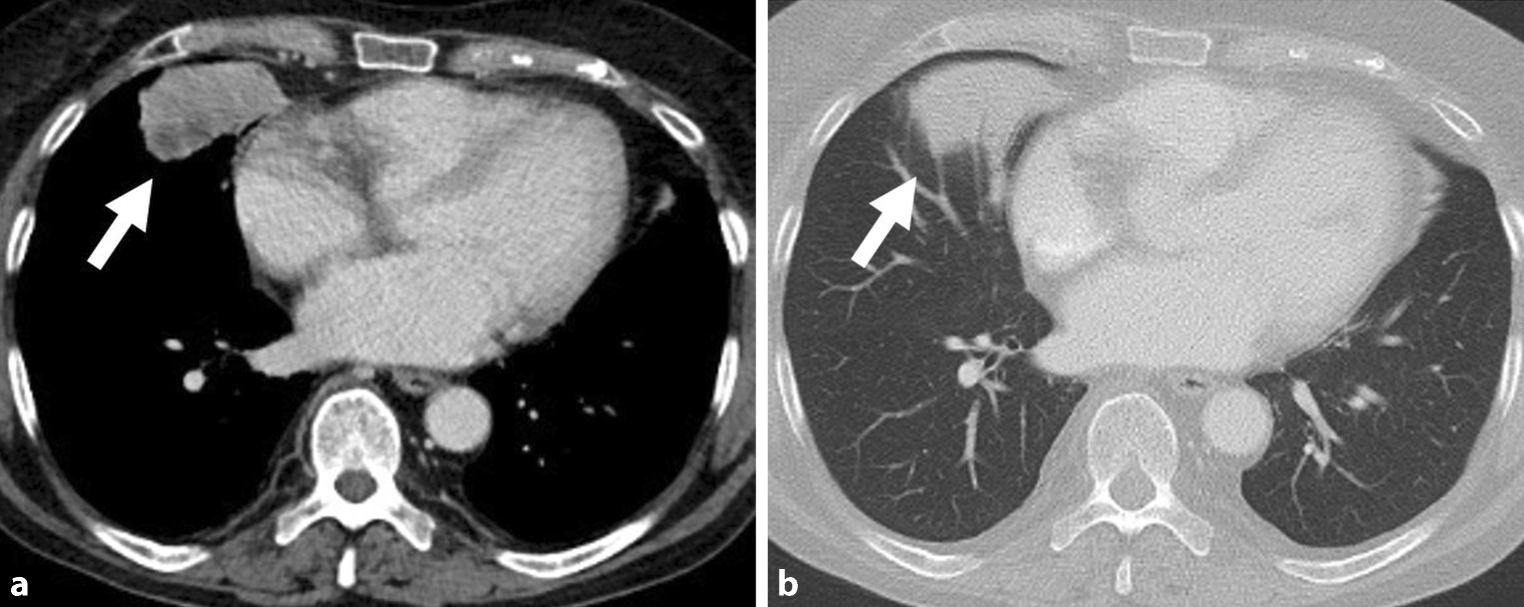

Following a full medical examination after a syncope a 66-year-old woman was diagnosed with a mass in the right lung after the basal portion of the tumour was visible in the standardly performed abdominal imaging. A computed tomography (CT) scan of the chest identified a tumour with a dimension of 55 × 44 mm in the peripheral medial middle lobe of the lung, directly associated to the pericardial adipose tissue and diaphragm. The tumour mass showed homogenous CT contrast agent enhancement (Fig. 1).

Fig. 1

Radiological features of primary pulmonary sarcoma (PPS): Contrast-enhanced computed tomography (a soft tissue window, b lung window) shows a subpleural lesion in the medial segment of the middle lobe with a dimension of 5.5 × 4.4 cm (arrow) directly associated to the pericardial adipose tissue